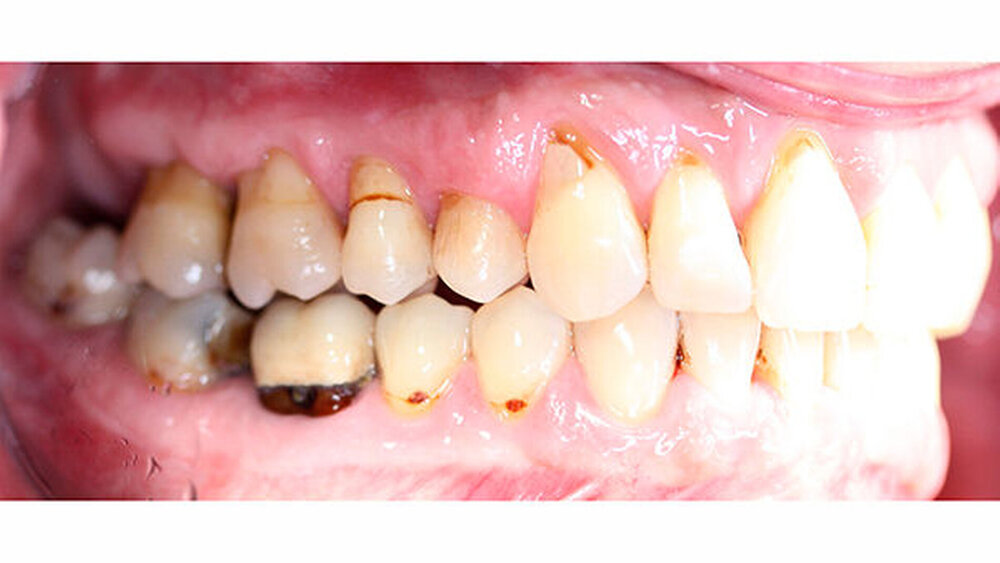

Röntgenologisch stellte sich im Orthopantomogramm der bereits intraoral ersichtliche horizontale und vertikale Knochenabbau mit Attachmentverlust an einzelnen Zähnen dar. Die Erhaltungswürdigkeit einzelner Zähne war aufgrund des starken Knochenverlustes beziehungsweise der Beeinträchtigung des Halteapparates als kritisch zu beurteilen.

Zudem wurde die Diagnose einer Parodontitis gestellt, die eine Rücküberweisung an den Hauszahnarzt erforderlich machte (Abbildung 2).